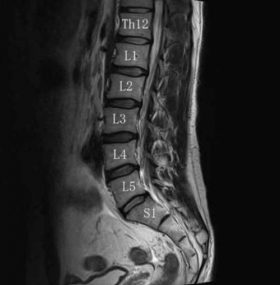

ぎっくり腰で病院を受診し、レントゲンやMRIを撮ると**「軽いヘルニアがありますね」**と言われることがあります。

最新の研究報告では、**「腰痛がない健康な人の85%に、椎間板の変性(ヘルニア等)が見つかる」**という衝撃的なデータがあります。

つまり、診断されたヘルニアは「今回のぎっくり腰で発生したもの」ではなく、**「もともと以前からあったもの」**である可能性が非常に高いのです。

ヘルニアがあることと、今感じている激痛は、必ずしも一致しません。